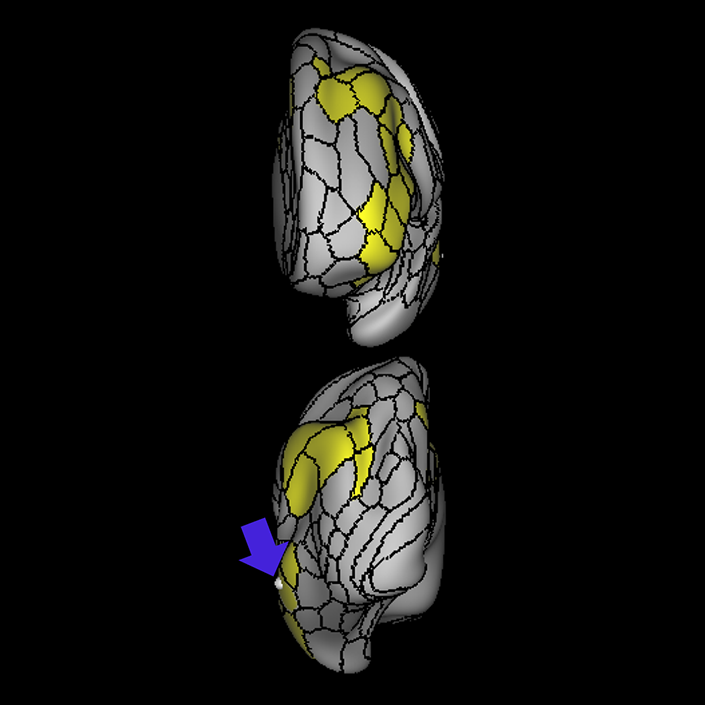

ᐅ SummaryArea 44: part of the inferior frontal gyrus of the lateral frontal lobe. Translates abstract and intentional information in the prefrontal cortex to more detailed representations to help guide the production of verbal and manual actions. In addition to its known association with Broca's area, is sometimes represented as part of Broca's complex ᐅ Where is it?Area 44 is at the posterior most part of the inferior frontal gyrus. It is the anterior bank of pars opercularis of the IFG. ᐅ What are its borders?Area 44 borders area 45 anteriorly and area 6r posteriorly. Area 8C is its medial border and its inferior border is wedged between then upper borders of Areas 6R and 6V. Its superior edge borders IFSp and IFJa. Its opercular surface is FOP4. ᐅ What are its functional connections?Area 44 demonstrates functional connectivity to areas SFL, IFSp, IFJa, 45, 47s, 47L, 9a, 9m, 8AV, 8BL and 8C in the dorsolateral frontal lobe, area 8BM in the medial frontal lobe, area 55b in the premotor areas, areas FOP5, AVI and PSL in the insula- opercular region, areas TGd, STSdp and STSvp in the temporal lobe, areas PFm, and PGi in the inferior parietal lobe, and no areas in the medial parietal lobe. ᐅ What are its white matter connections?Area 44 is structurally connected to the arcuate/SLF and the FAT. Connections with the arcuate/SLF project posteriorly and wrap around the Sylvian fissure to the middle temporal gyrus to end at TE1a and TE1m. There are also projections from the arcuate/SLF before it terminates to parcellations A5 and STSdp. The majority of the inferior connections of the frontal aslant tract end at 44, the tract is connected superiorly to superior frontal gyrus parcellations SFL, 6ma and s6-8. Local short association bundles are connected with 45 and 8C. White matter tracts from 44 in the right hemisphere have less consistent connections with the arcuate/SLF. ᐅ What is known about its function?Area 44 translates abstract and intentional information in the prefrontal cortex to more detailed representations to help guide the production of verbal and manual actions. Area 44, in addition to its known association with Broca's area, is sometimes represented as part of "Broca's complex", including Brodmann Areas 45, 46, 47 and the mesial supplementary motor area of 6, which contribute to a frontal-subcortical circuit. The right pars opercularis has also been implicated in cognitive inhibition in the overall context of working memory. |

A: lateral-medial

B: anterior-posterior

C: superior-inferior

DTI image |